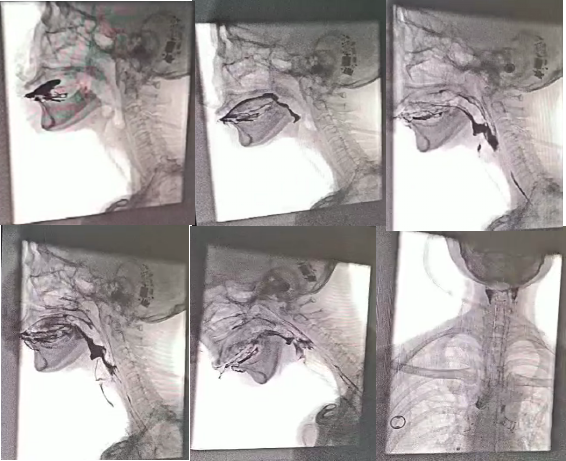

叶阿姨入院后,该院康复医学科的主管医生迅速对她进行了初步康复评估,认为她存在严重的吞咽障碍,需要进行更系统的吞咽评估,于是安排叶阿姨做了吞咽造影。在检查室里,叶阿姨分别吃下四种不同形状的食物,医生和康复治疗师通过照影观察发现,她的梨状隐窝存在大量食物残留,环咽肌开放不全,并且还有隐形误吸,不允许经口进食。

据介绍,吞咽造影检查是在X线下,针对口、咽、喉、食管的吞咽动作所进行的特殊造影,该方法可以对整个吞咽过程进行详细的评

估和分析,对研究吞咽障碍的机制和原因具有重要的价值,因此,吞咽造影被认为是吞咽障碍检查的理想方法和诊断的“金标准”。